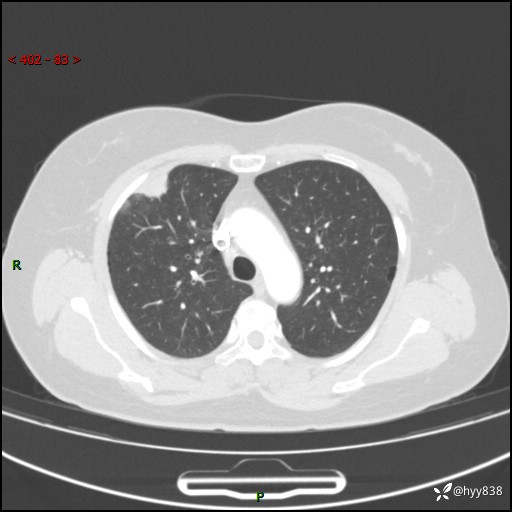

中年女性,间断胸痛2天。“又见”胸膜下团块,性质难定---结果公布~

现病史:患者于2天余前无明显出现间断胸痛,无头痛、头晕,无心慌、胸闷、胸痛、呼吸困难、低热、盗汗,无腹痛、腹胀等不适,未进行进一步诊治。于2024.04.14在当地市人民医院行胸部CT检查提示:右肺上叶胸膜下结节。现患者为求进一步诊治,来我院就诊。以“肺肿物”收入我科。 患者自起病以来,精神可,睡眠可,饮食可,大小便正常,体重无明显改变。

胸部CT增强(肺窗,外院平扫)